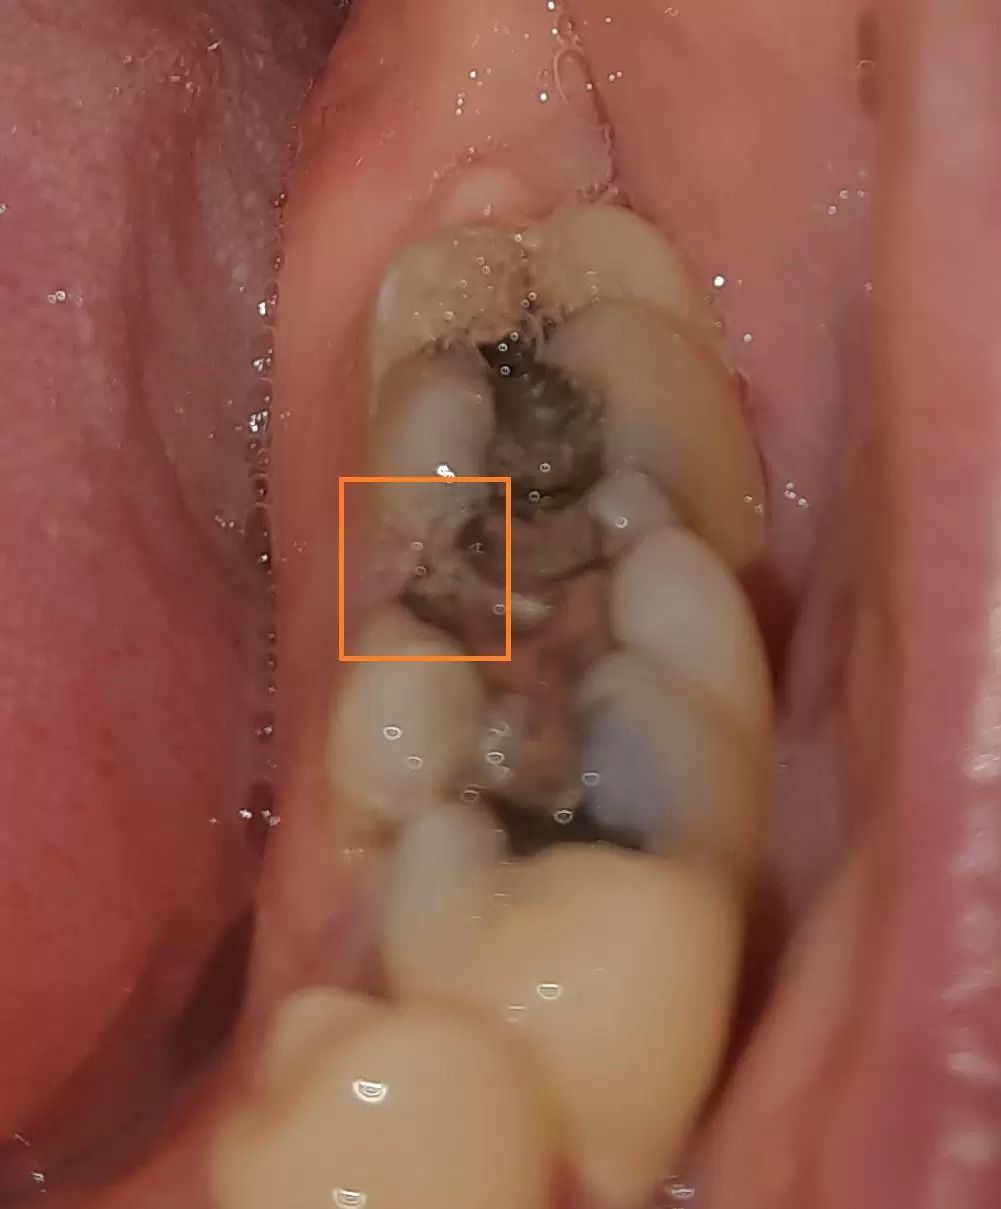

na stoličke, na které mám velkou amalgámovou plombu se mi ulomila část zubu (ten jeden výběžek zubní korunky, viz obrázek). Korunku moc na zdravý zub zhotovovat nechci, vrtat obrovskou amalgamovou plombu a pokoušet se dát na ní bílou plombu mi nepřijde taky rozumné, zub by se mohl roztrousit během vrtaní celý příp. by se možná došlo až k nervům a znamenalo by to pak rozsáhlejší opravu. Nedá se ta část zubu bez odstranění amalgámové plomby dotvarovat bílou resp. znova amalgámovou plombou? Jinak zub neboli, celý čas jsem s ním neměl problém, byla by škoda o něho přijít. Děkuji.